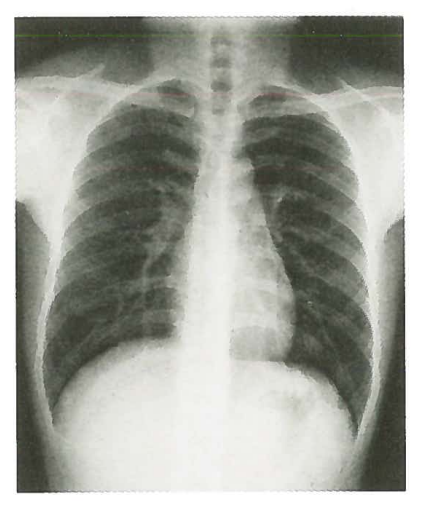

X射线成像是一个覆盖图像,即从X射线照射部分的前后到后面的所有图像的叠加,就像“感应眼”的角度。因此,X射线成像也称为荧光镜检查。例如,用于学校体格检查的“胸部荧光镜”项目,公务员和公共机构的参加体格检查是指胸部来回的X射线成像,但它不显示电影中的图像,成像板和平板电脑。在检测器中,它直接在荧光屏幕上显示以实时观察。下图是胸部来回的X射线图像,这表明胸部的所有组织结构都叠加在图像中。

图片来自第九版的Renwei医学成像

X射线射击很方便,成本较低。单个扁平膜的价格约为100元,并且成像显示范围相对较大(如上图所示,您可以看到整个胸部)。缺点是,作为一个叠加的图像,多层组织的成像叠加可能会影响病变的判断,并且很难检测到一些细微的病变。此外,由于组织的特征和X射线成像的原理,X射线的应用范围有限:例如,在临床实践中,腹部很少使用平坦的X射线开元棋官方正版下载,通常是仅用于急性腹部症状,石头的主要筛查等;通过内窥镜检查,可以在腹部使用X射线平面,通常仅用于急性腹部症状,石头的主要筛查。随着技术的发展,钡餐检查的应用也有所下降。